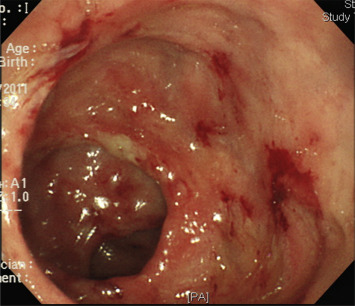

A 50-year-old man presented with progressive bloody diarrhea for 2 months. He was a businessman without systemic diseases. He had suffered from bloody diarrhea as frequently as four to five times per day since April, 2011. He visited a local hospital where a colonoscopy revealed pancolonic ulcerations with spontaneous bleeding (Fig. 1). The pathology report showed severe colitis with ulcers and focal crypt abscesses. UC was diagnosed. Sulfasalazine was given and his symptoms gradually improved. However, hypoalbuminemia and renal function deterioration developed 6 months later. Sulfasalazine was replaced with mesalamine. A colonoscopy in May 2012 revealed multiple ulcers scattered over the whole colon and rectum. The pathology report showed nonspecific colitis. As his bloody diarrhea and abdominal fullness progressed, he was referred to our hospital. Oral and suppository mesalamine were prescribed and his symptoms improved. Hypoalbuminemia (Alb: 3.2 g/dL), proteinuria (600 mg/dL), and renal insufficiency (Cre: 1.6 mg/dL) were still noted. His autoimmune profile, including C3, C4, IgA, ANA, p-ANCA, and c-ANCA, were all normal. A renal biopsy was suggested, but the patient refused. Under the impression of nephrotic syndrome, prednisolone (50 mg/day) was used, starting in March 2013. His proteinuria and hematuria partially improved and his case was followed up at the original hospital.

Figure 1. Colonoscopy image showing diffuse inflammatory mucosa associated with multiple ulcerations over the whole colon. |

We reviewed the patients previous data, endoscopic findings, and histological results. Neither typical, continuous, and confluent mucosal inflammation, ulcerations, granularity, nor loss of visible vascular pattern of the mucosa were present. The initial pathology report revealed the presence of ulcers with focal crypt abscesses, which were nonspecific features of colitis. Furthermore, when the slides were reviewed again, the initial biopsy revealed the presence of amebic trophozoites. Therefore, if the slides had been examined in more detail, the correct diagnosis may have been made earlier.